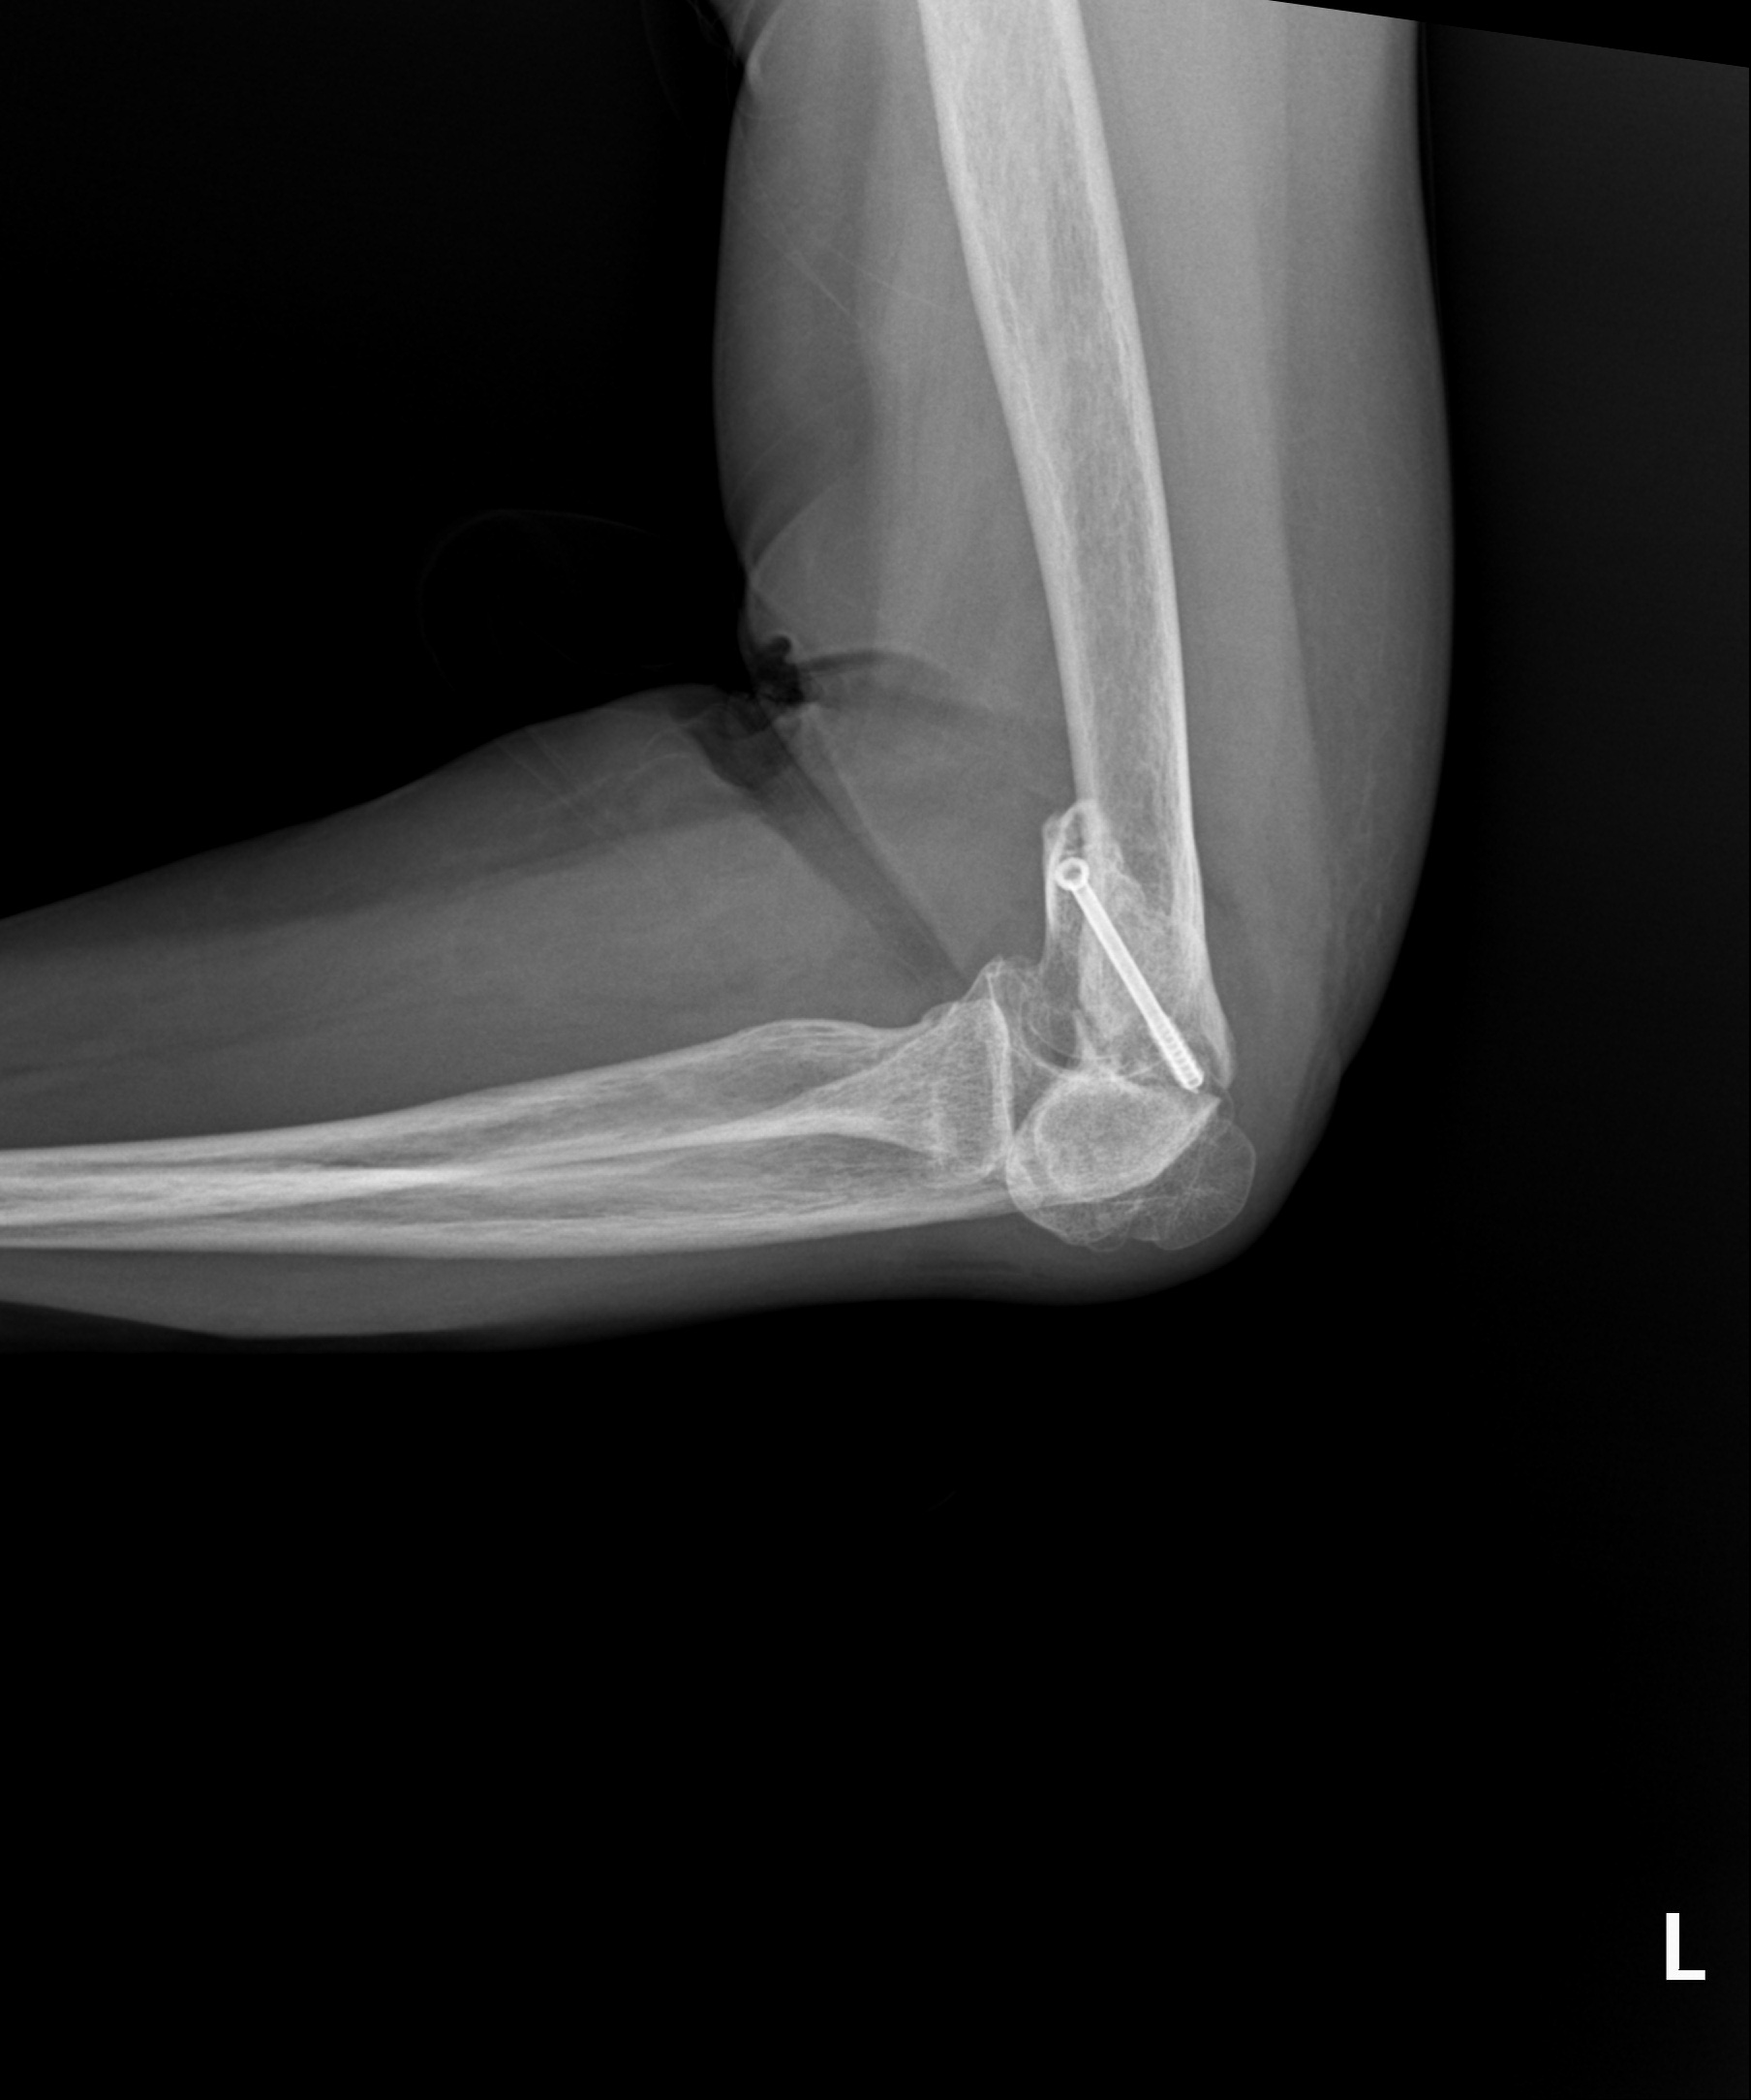

고난도 골절

2023.03.24

2023.03.31

원위 상완골 골절

2022.07.14

2023.02.07